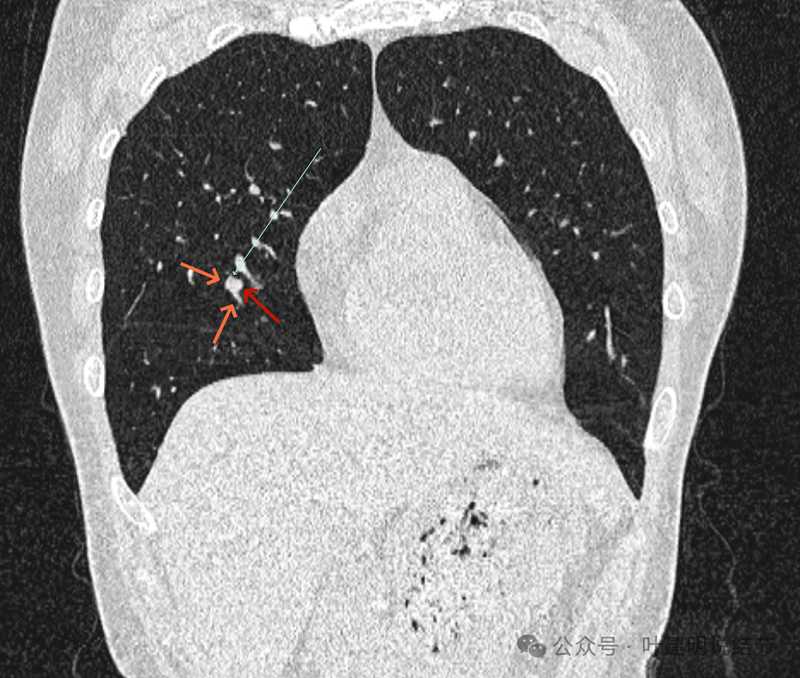

再看冠状位影像:

血管与病灶的关系,两者密度稍不同,天蓝色细箭头所指是分界线。

血管征明显。

血管围着病灶,病灶有膨胀性,表面欠平滑。

不而有膨胀性,血管贴着并被压迫。

边缘欠平滑,邻近血管间隙欠清晰。

血管贴着,结节膨胀。

也示血管与病灶的关系。

结节实性。

纵隔窗这个角度明显见到蓝色箭头所指的血管被病灶侵蚀,而且血管与病灶密度的不同。